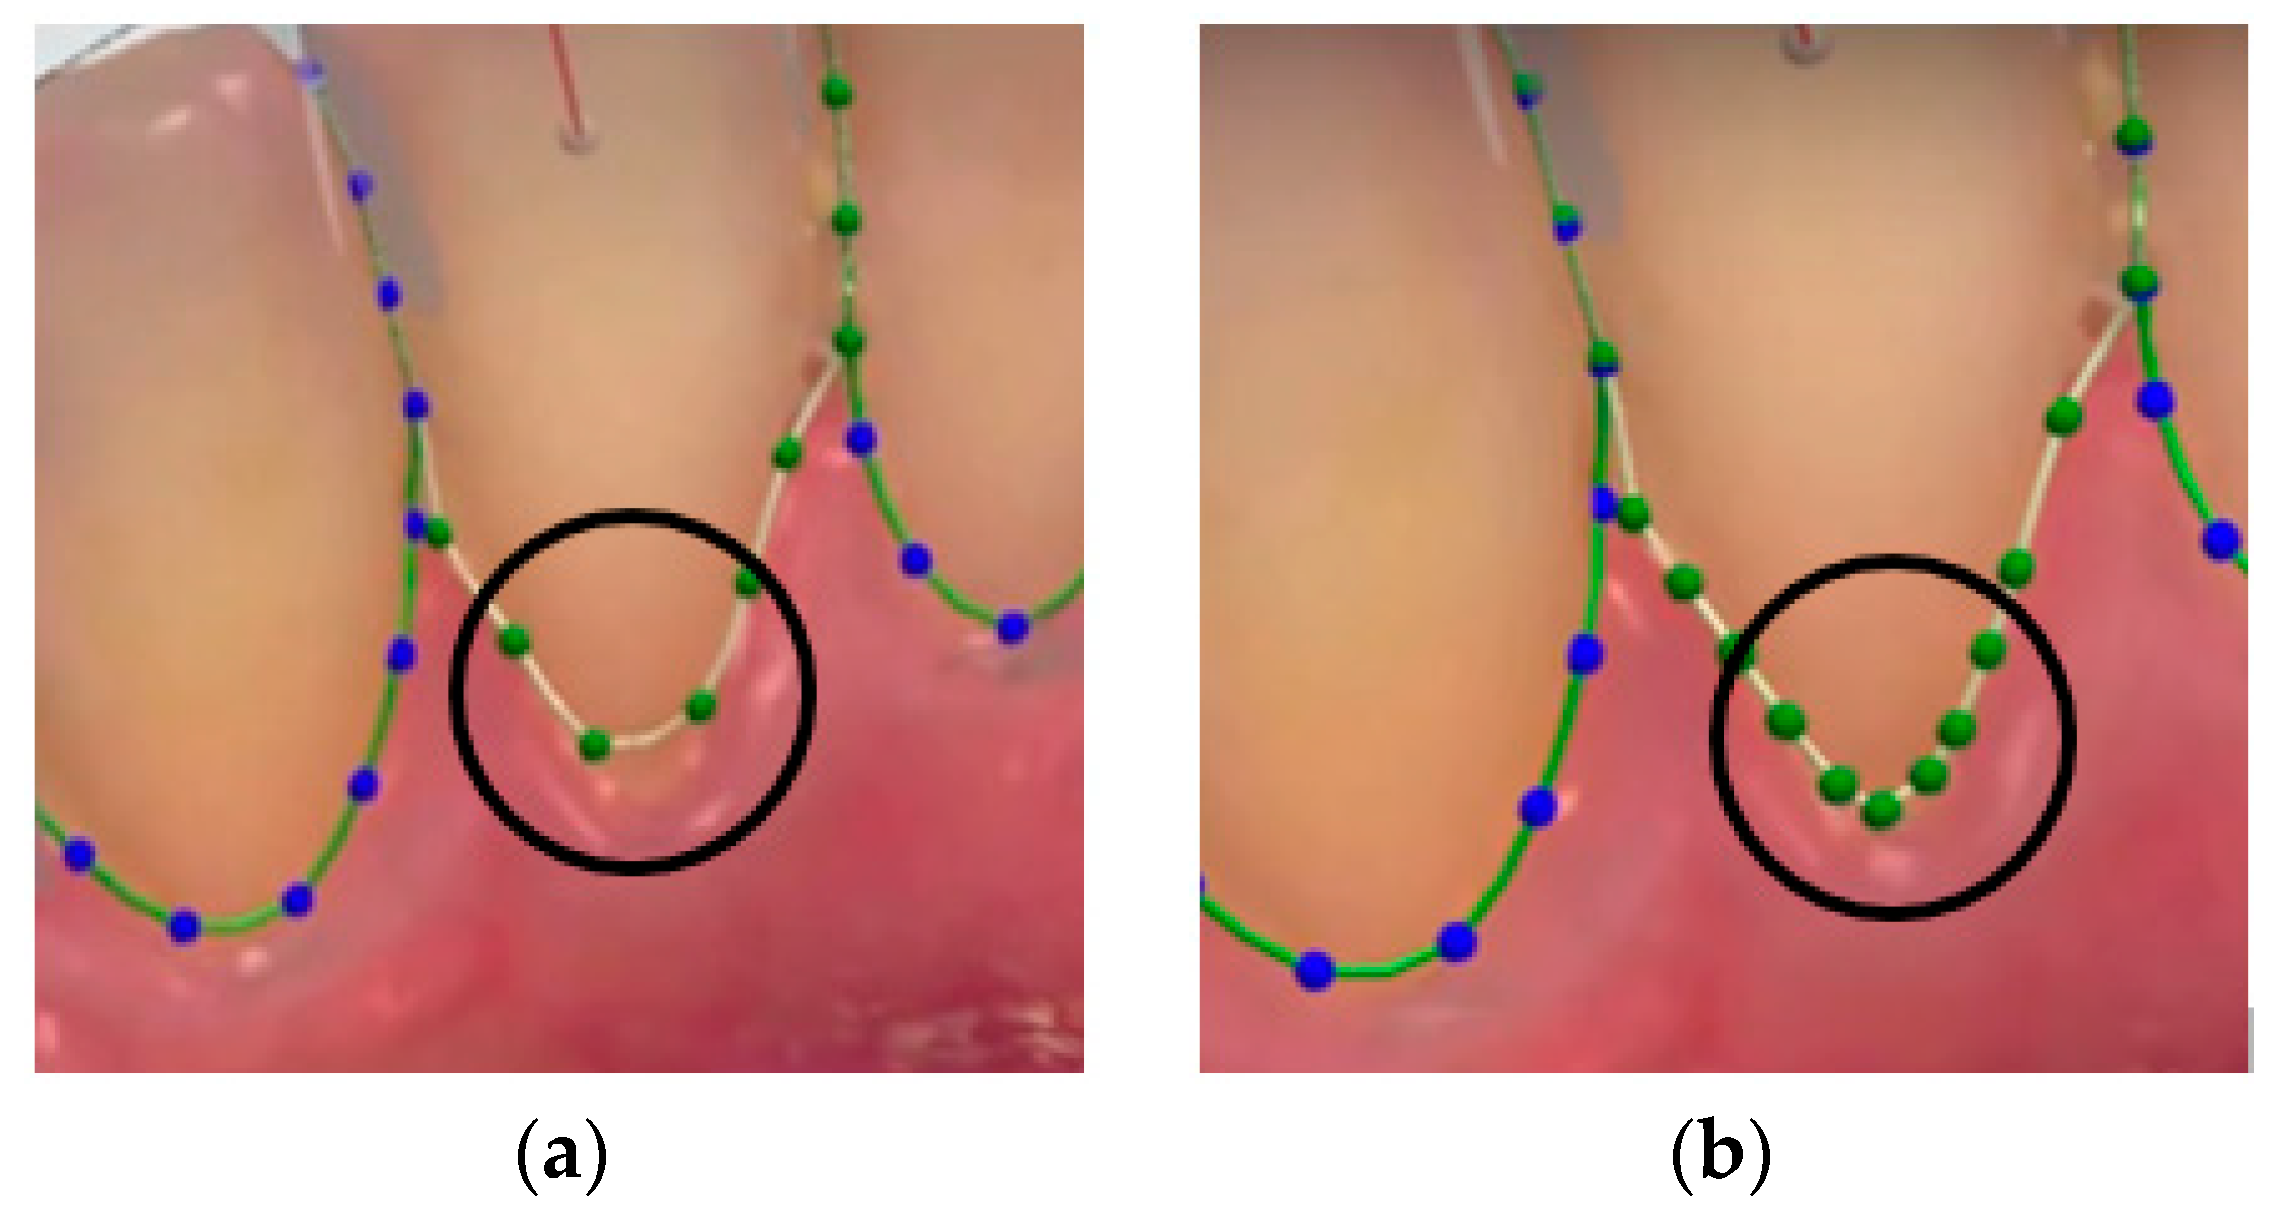

1.1.2. Tooth Segmentation

2.1. Overview

2.2. Reconstruction of Dental Scan Data

2.3. Training GAN

2.3.1. Data Preparation

2.3.2. Training Steps